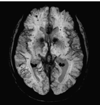

Brain regulation of thrombosis and hemostasis: from theory to practice

Keywords: blood-brain barrier; hemorrhage; hemostasis; thrombosis.